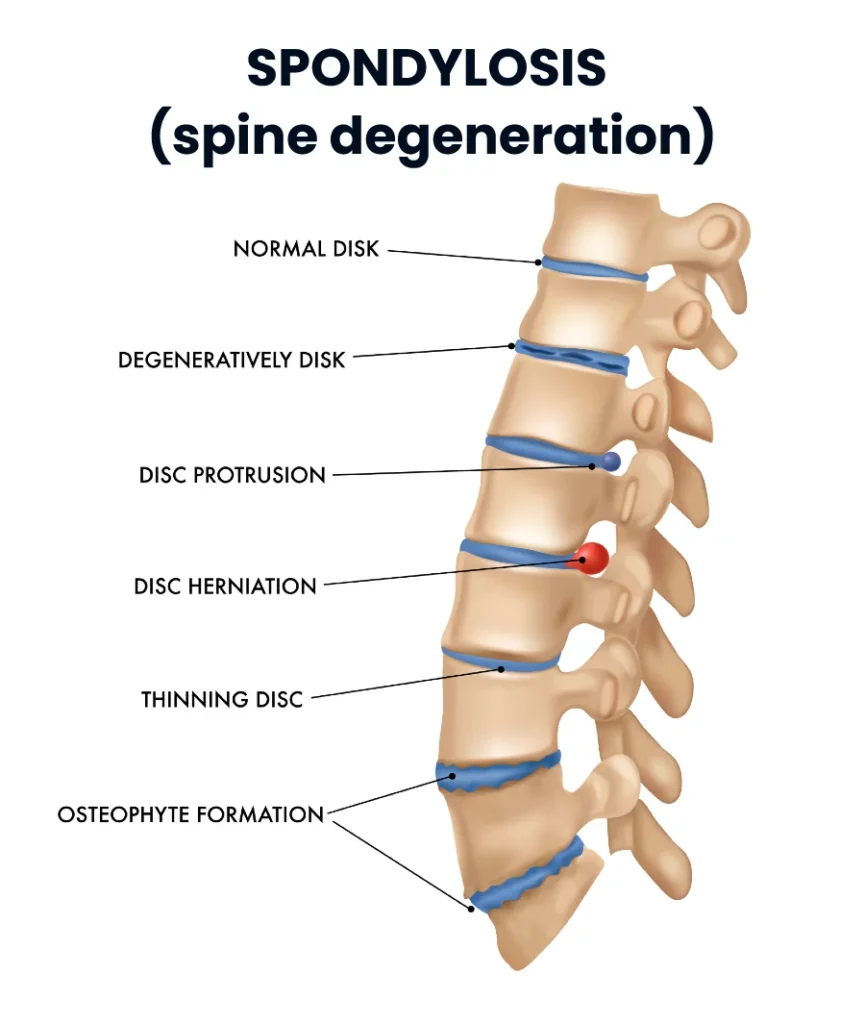

Spondylosis is a broad medical term used to describe degenerative changes of the spine. These changes include the gradual wear and tear of the intervertebral discs, the formation of bony growths (osteophytes), and a reduction in spinal mobility.

As mentioned earlier, degenerative changes associated with spondylosis can involve any spinal structure.

Below is an overview of the main pathological processes that occur in different parts of the spine in spondylosis, along with definitions of key related terms.

Osteophytes (Spondylophytes)

Osteophytes are bony outgrowths that form along the edges of vertebral bodies as a response to chronic mechanical stress and loss of spinal stability, usually resulting from degeneration of the intervertebral discs and facet joints.

Although osteophytes are often asymptomatic, their enlargement may lead to narrowing of the spinal canal or intervertebral foramina, potentially causing neurological symptoms due to nerve compression.

Degenerative Disc Disease

Degenerative disc disease refers to progressive structural changes of the intervertebral discs caused by aging and mechanical loading. These changes include:

- Loss of water content in the disc nucleus

- Reduction in disc height

- Development of fissures in the outer disc ring

As a result, disc degeneration may lead to disc herniation, reduced space between adjacent vertebrae, and segmental mechanical instability.

Facet Joint Osteoarthritis (Spondyloarthrosis)

Facet joints are paired joints located at the back of the spine and are structurally similar to other synovial joints in the body. Degenerative changes of these joints include:

- Thinning of the articular cartilage

- Formation of osteophytes

- Thickening of the joint capsule

These changes can contribute to spinal stiffness, pain, and reduced mobility.

In conclusion, spondylosis refers to degenerative processes affecting the spine, characterized by:

- Formation of osteophytes

- Degeneration of intervertebral discs

- Osteoarthritis of the facet joints

- Thickening of spinal ligaments

Together, these changes may alter spinal biomechanics and, in some cases, lead to pain, stiffness, or neurological symptoms.